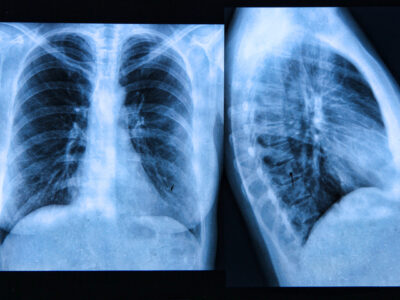

Former Grateful Dead keyboardist Tom “TC” Constanten is now in the fight of his life—this time against lung cancer. At 80 years old, the legendary musician is facing not only serious health concerns but also mounting medical bills. Now, the same community that once embraced his experimental sound is rallying behind him with unwavering support …